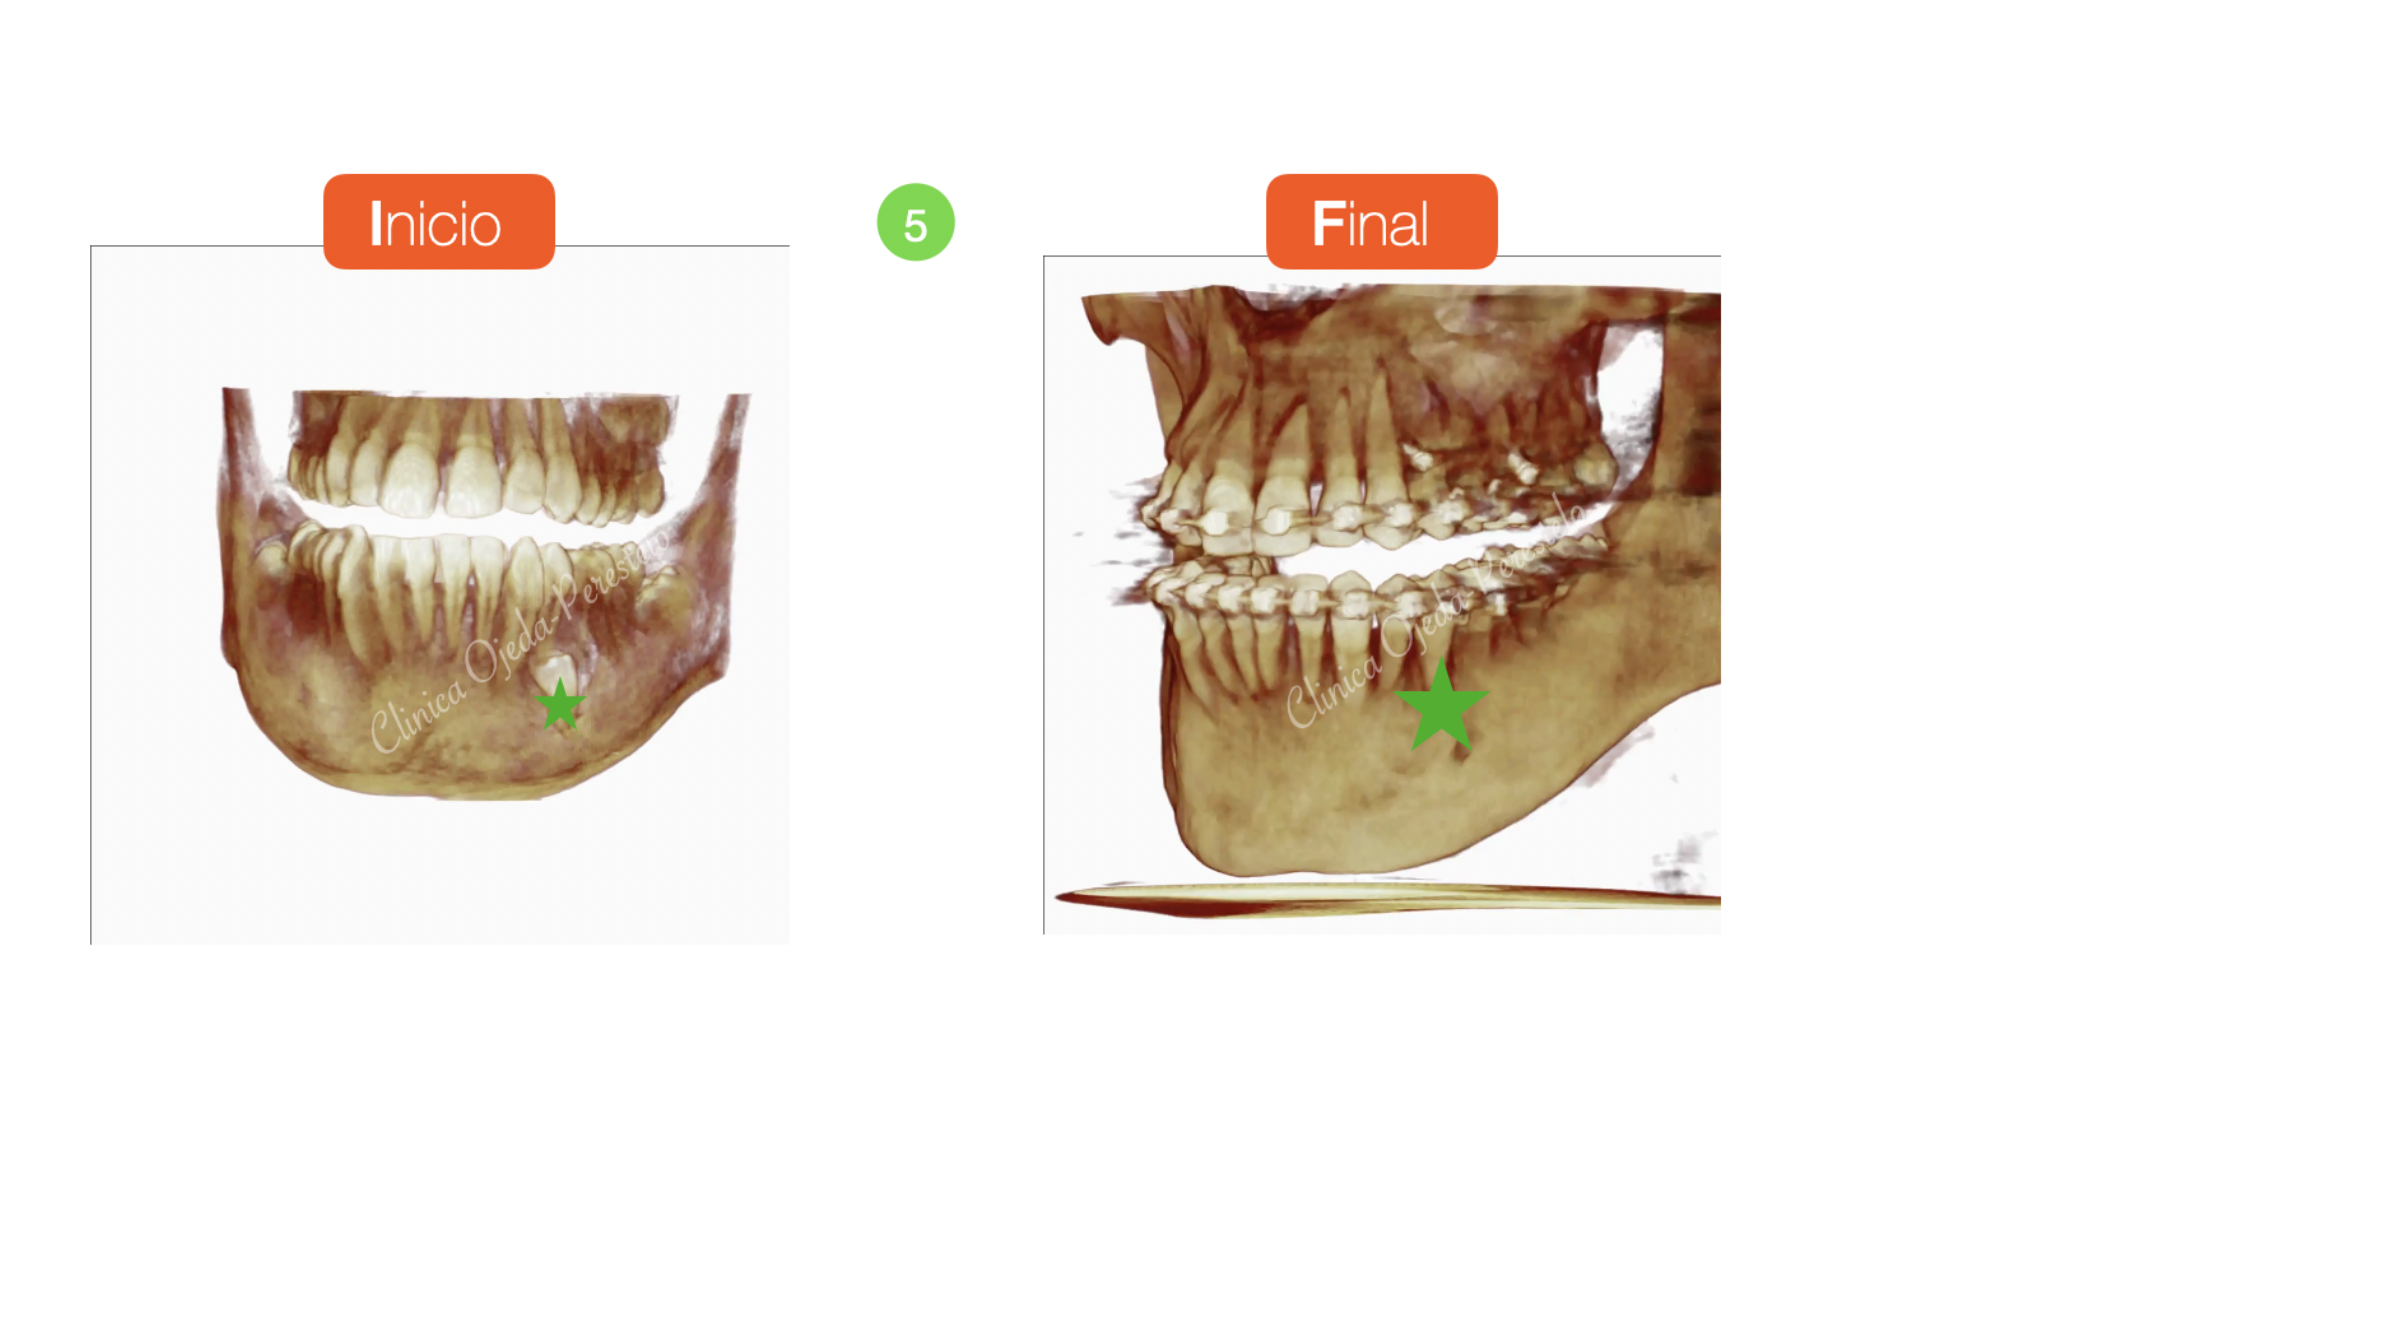

Su estudio detallado nos confirma  que se encuentran próximo al borde mandibular y por la cara vestibular. Decidimos fenestrarlo e implementar una combinación de vectores extrusivo-distal y lingual hasta su correcta reubicación dentro de la arcada utilizando como anclaje 1MT con un resorte fabricado a medida. Este protocolo nos permite proteger de posibles reabsorciones radiculares a los dientes de apoyo.